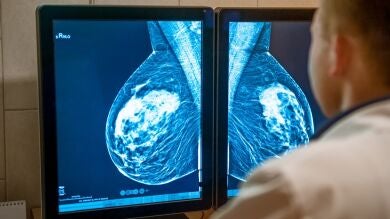

Cáncer de mama

El cáncer de mama es una enfermedad de la glándula mamaria que se produce cuando las células crecen y se multiplican de forma anormal. Es el cáncer más frecuente entre las mujeres.

Como ella, más de 30.000 mujeres son diagnosticadas al año de cáncer de mama. Lo tendrán una de cada 8 mujeres a lo largo de su vida, dice la radióloga mamaria Silvia Pérez.

Es elmás frecuente entre las mujeres y cada vez comienza antes, a partir de los 40. Las causas, según la doctora Pérez: "Mala alimentación, falta de ejercicio físico, fumar, alcohol, etc"

La prevención sigue siendo la mejor arma, no hay que olvidar que UN alto porcentaje (un 85%-90) de los casos se curan si se detectan a tiempo.